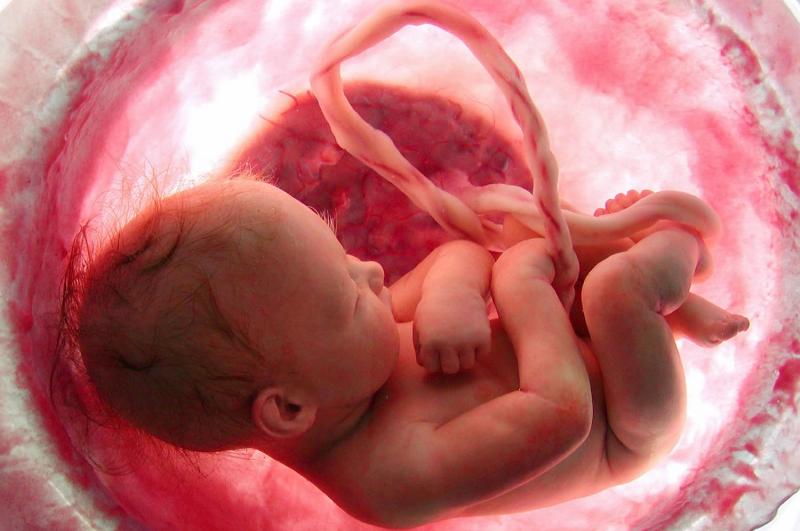

پارسینه: قلب جنین چه زمانی تشکیل میشود؟ چه عواملی باعث تشکیل نشدن قلب جنین میشود؟ در اینجا با مقالهای درباره بارداری هفته به هفته، علل تشکیل نشدن قلب جنین در خدمت شما هستیم.

در این مقاله قصد داریم شما را با یکی از مهمترین دغدغههای زنان در هفتههای اول بارداری آشنا کنیم. تشکیل قلب جنین یکی از مهمترین فرآیندهای رشد جنین محسوب میشود و در واقع موجودیت جنین بستگی به این موضوع دارد. در ادامه با خوراکیهایی که در تشکیل شدن قلب جنین نیز موثر میباشند آشنا میشوید.

مهمترین مساله ایی که احتمال بارداری را تقویت میکند تشکیل قلب جنین است. بسیاری از مادران در هفتههای چهارم و پنجم برای سونوگرافی واژینال مراجعه میکنند تا از بارداری داخل رحم مطمئن شوند. این آزمایش در هفته پنجم بارداری صورت میگیرد و در طی آن مشخص میشود که ساک بارداری تشکیل شده است. البته جنین هنوز مراحل رشد اولیه را طی میکند و قابل مشاهده نیست. به همین دلیل ممکن است بسیاری از زنان برای تشکیل جنین نگران شوند. بعد از هفته هفتم بارداری کم کم قلب جنین تشکیل شده با این حال نمیتوان در این زمان نیز جواب قطعی گرفت.

مراحل و زمان تشکیل قلب جنین

در صورتی که در هفته هفتم بارداری هنوز اثری از تشکیل قلب جنین مشاهده نشد میتوان آن را دلیل بر عدم بارداری دانست. مراحل رشد جنین ۱۲ ماه به طول میانجامد بنابراین برای تشکیل اندامها و بویژه قلب جنین نباید عجله داشت. به زنان باردار توصیه میشود که برای گرفتن جواب دقیق و اطمینان بیشتر در هفته دوازدهم برای آزمایش اسکن مراجعه کنند. در هفته دوازدهم جنین و قلب تشکیل شده و صدای قلب جنین نیز واضح است.

تشکیل قلب جنین با نبض آغاز میشود که در هفتههای اولیه بارداری خصوصا هفتههای ششم تا هشتم ضربان قلب جنین به راحتی تشخیص داده نمیشود. اگر هیچ ضربان قلبی شنیده نشد اسکن باید مجددا چند هفته بعد تکرار شود. در هفتههای هشتم تا دهم بارداری ضربان قلب جنین به طور واضح شنیده میشود. رشد جنین در این مرحله هنوز کند بوده و جثه کوچکی دارد. در این مرحله باید مراقبتهای ویژه ایی به عمل آید تا از خون ریزی جلوگیری شود. بین هفتههای دهم تا دوزادهم بارداری جثه جنین بزرگتر شده و اندامها تشکیل میشوند. در این مرحله اندامهایی مانند سر و بدن جنین بزرگتر میشود.

زمان و مراحل تشکیل قلب جنین

صدای قلب جنین یکی از آرامش بخشترین صداها برای مادراست و هیچ احساسی زیباتر از این نیست که بدانید زندگی در رگها جنینتان جریان دارد

قلب در اولین مراحل رشد جنین تشکیل میشود و از اولین اعضای بدن جنین است که رشد و شروع به ضربان میکند و با هر تپشش حس زندگی را در مادر باردار زنده میسازد، ولی آیا میدانید قلب جنین هفته چند بارداری تشکیل میشود؟

قلب جنین در کدام هفتهی بارداری تشکیل میشود؟

ازمهمترین مراحل رشد جنین تشکیل قلب اوست که هم زمان با تشکیل قلب برخی از اجزای بدن جنین نیز ساخته میشوند؛ قلب جنین از اولین روزهای تشکیل خود ضربان دارد و از اولین هفته حاملگی خون را به بدن جنین در حال رشد پمپاژ میکند.

مراحل تشکیل قلب جنین

قلب جنین در هفته شش بارداری تشکیل میشود و شروع به ضربان میکند. قلب جنین در این هفته ۸۰ بار در دقیقه میزند و دارای چهار حفره عمیق است که هر حفره دارای مسیر ورودی و خروجی مختص خود برای داخل و خارج شدن خون است.

طول جنین حدود ۸ میلی متر (۱/۴ اینچ) است.

نخاع جنین که باز بوده شروع به بسته شدن میکند.

رشد سلولهای خون و رگهای خونی آغاز میشود.

این رگهای خونی خون را به رحم میرسانند.

قلب لوله شکل تشکیل میشود و شروع به ضربان زدن میکند. قلب جنین ابتدا به شکل یک لوله ساده است که طی چند هفته رشد کرده و به یک عضو چهار حفرهای و دارای مسیرهای خروجی و مجرای بازگشت سیاهرگی تبدیل میشود.

قلب از سلولهای اختصاصی واقع در حداقل دو قسمت از بدن جنین رشد میکند. این سلولها با هم ترکیب میشوند تا قلب لولهای شکل اولیه را تشکیل دهند. با گذشت زمان برخی از قسمتهای آن رشد کرده و تحت فرآیندی بنام حلقه زنی قلب قرار میگیرند تا ساختار نهایی قلب را تشکیل دهند.

مغز به ۵ قسمت تقسیم میشود.

تشکیل چالههای نوری از چشم آغاز میگردد.

سلولهای دست و پا در جای خود قرار میگیرند.

در چه مرحلهای از بارداری برای اولین بار صدای قلب جنین را میشنویم؟

در هفتههای ابتدایی بارداری، زنان باردار به علت تشکیل اندامهای اصلی جنین خسته و بی حال هستند و برخی از آنان دچار ویار بارداری میشوند و به حالت تهوع و سردرد دچار میشوند. زنان باردار در این زمان برای کمک به رشد جنین، نیاز به استراحت زیاد، هوای آزاد، ورزش منظم و رژیم غذایی سالم دارند.

در این زمان تمامی اندامها تشکیل میشود، اما هنوز کامل نشده است. یکی از اندامهایی که تشکیل شده قلب است که بعد از شش هفته بعد از آخرین پریودی شروع به تپش میکند. در این هنگام جنین از کشمش کوچکتر است و در دو طرف سرش گوش هایش تشکیل شده است.

در این زمان جنین از کشمش کوچکتر است. پایین در دو طرف سر دو بافت وجود دارد که گوشهای او است. اگر چه اندامها کامل نشده اند، اما تمام آنها تشکیل شده اند. قلب نیز تشکیل شده است و ۲۵ روز بعد از بارداری شروع به زدن میکند (شش هفته بعد از آخرین پریودی). ضربان قلب نیز در حال حاضر قابل تشخیص است.

نخاع و ستون فقرات در این مرحله رشد میکنند و ظاهر آنها شبیه دم است که با رشد جنین این قسمت از بین میرود. لوله عصبی که شامل سه بخش است رشد میکند و مغز را تشکیل میدهد. جفت نیز اکسیژن و موادغذایی لازم رابه جنین میرساند.